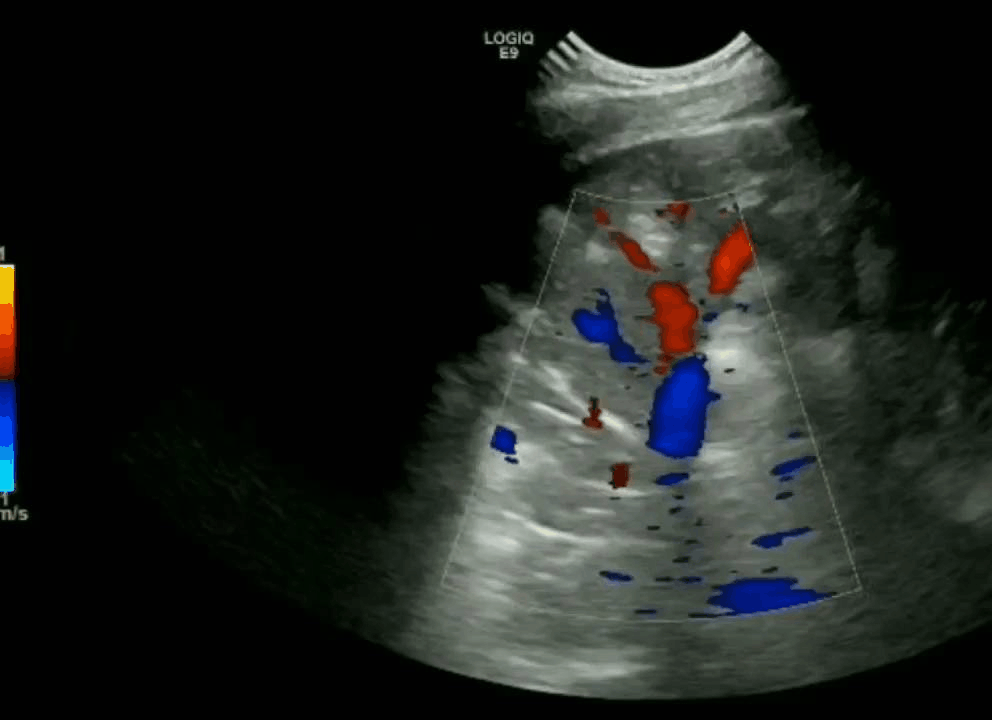

Consolidation

Hepatization of the lung parenchyma due to infiltration with fluid. May also have “air-bronchograms”.

Color doppler will show blood flow through the pulmonary vasculature.

In alveolar consolidation the lung parenchyma takes on the appearance of liver echotexture, “hepatization”. There may be air bronchograms present in consolidated tissue which appears as hyperechoic air bubbles with reverberation artifacts. Color doppler will show blood flow through the pulmonary vasculature.